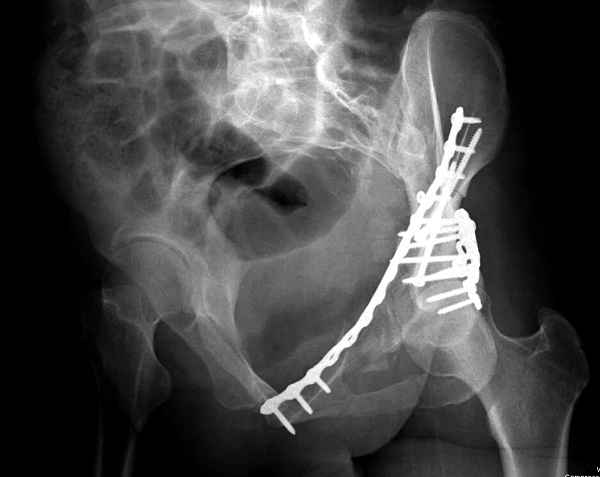

Здесь несколько вариантов двухколонных свежих переломов, которые были оперированы из одного-заднего, а также из двух: переднего и заднего доступов.